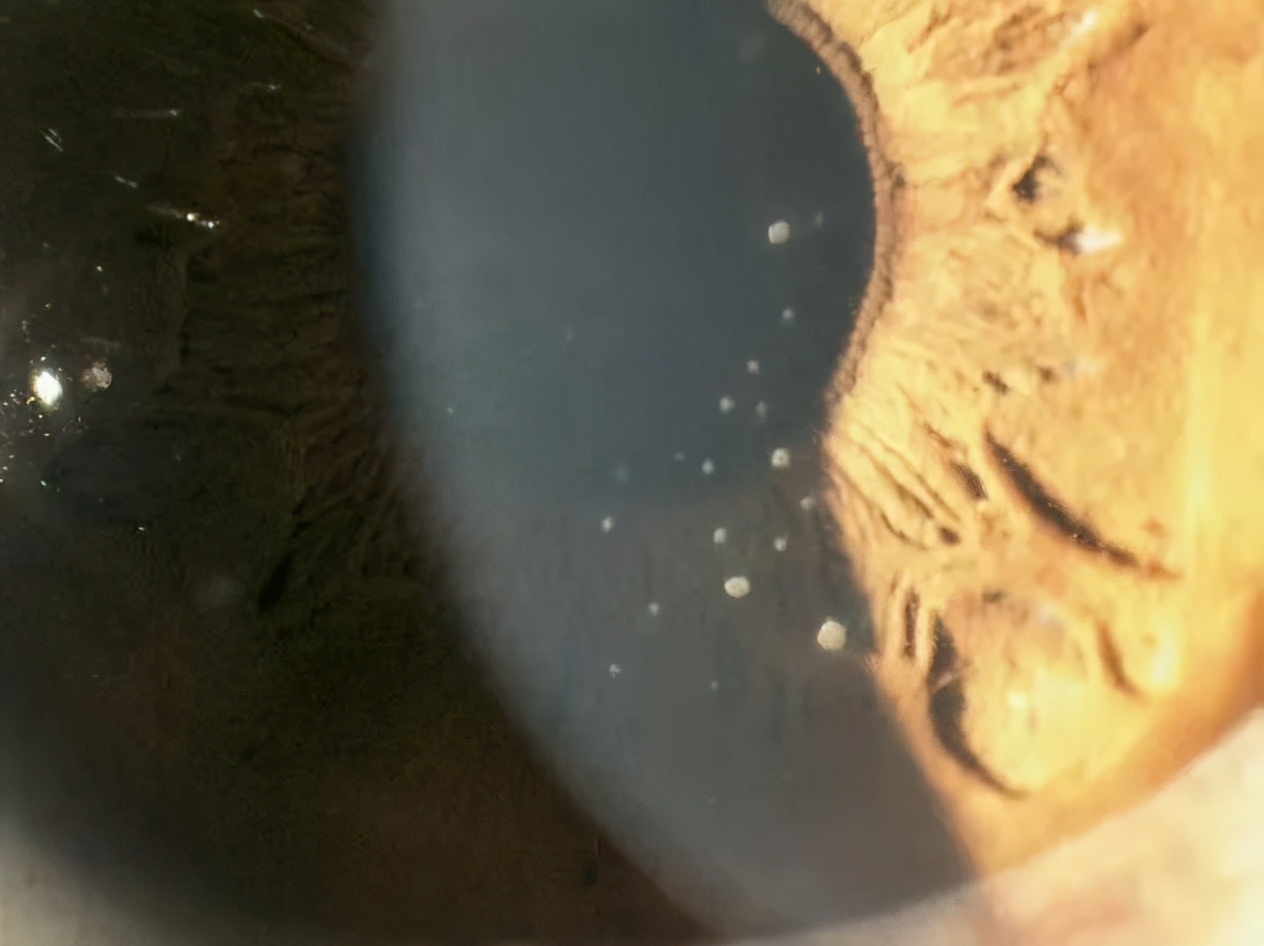

小洁右眼眼压高达55mmHg(正常眼压是10-21mmhg),右眼球结膜轻度充血,角膜上皮雾状水肿,角膜后下方见数枚羊脂状沉着物, 确诊为青光眼睫状体炎综合征。

角膜后下方见数枚羊脂状沉着物